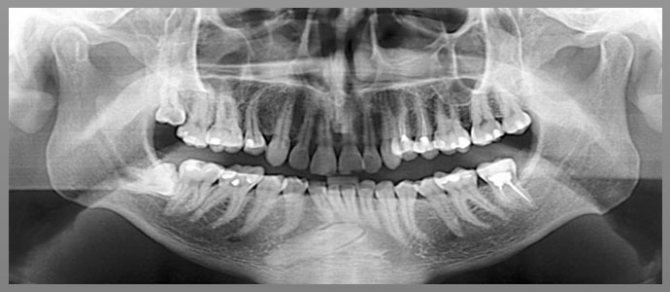

- рентген верхней и нижней челюсти — определяет поражение хрящевой и костной ткани;

- Рентгенография костей челюсти на начальных стадиях помогает определить прорастание опухолевой ткани в кость.

- Изменение структуры костной ткани. Она становится менее плотной, что приводит к частым переломам челюсти, возникающие даже при незначительных ударах. Также наблюдается появление свищей.

Диагностика зубного рака

Чаще всего происходит следующее. В ходе обращения пациента к стоматологу с жалобами, тот проводит первичный осмотр ротовой полости и в случае необходимости назначает рентгенологическое обследование.

В случае обнаружения в костной структуре посторонних элементов пациент отправляется на приём к онкологу, который должен вынести окончательный вердикт.

Диагностика ракового поражения зубов

Как правило, первоначальную диагностику рака зубов проводит врач-стоматолог во время осмотра ротовой полости. После оценки субъективных данных (жалоб пациента) и результатов визуального обследования производится рентгенологическое исследование. Если результаты дополнительных методов диагностики подтверждают наличие новообразования в костной структуре челюсти пациента направляют на консультацию к онкологу, который устанавливает окончательный диагноз.